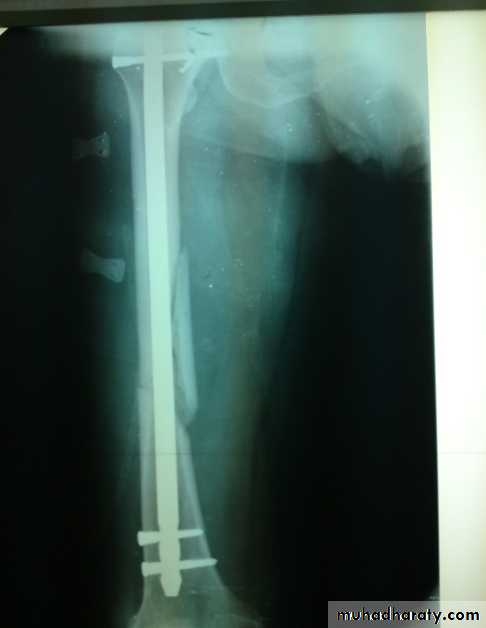

Intramedullary nail with interlocking screws is the method of choice

Treatment

Slightly displaced #s- skeletal traction through proximal tibia.If closed reduction fails- ORIF.

Locked intramedullary nail is the fixation of choice.